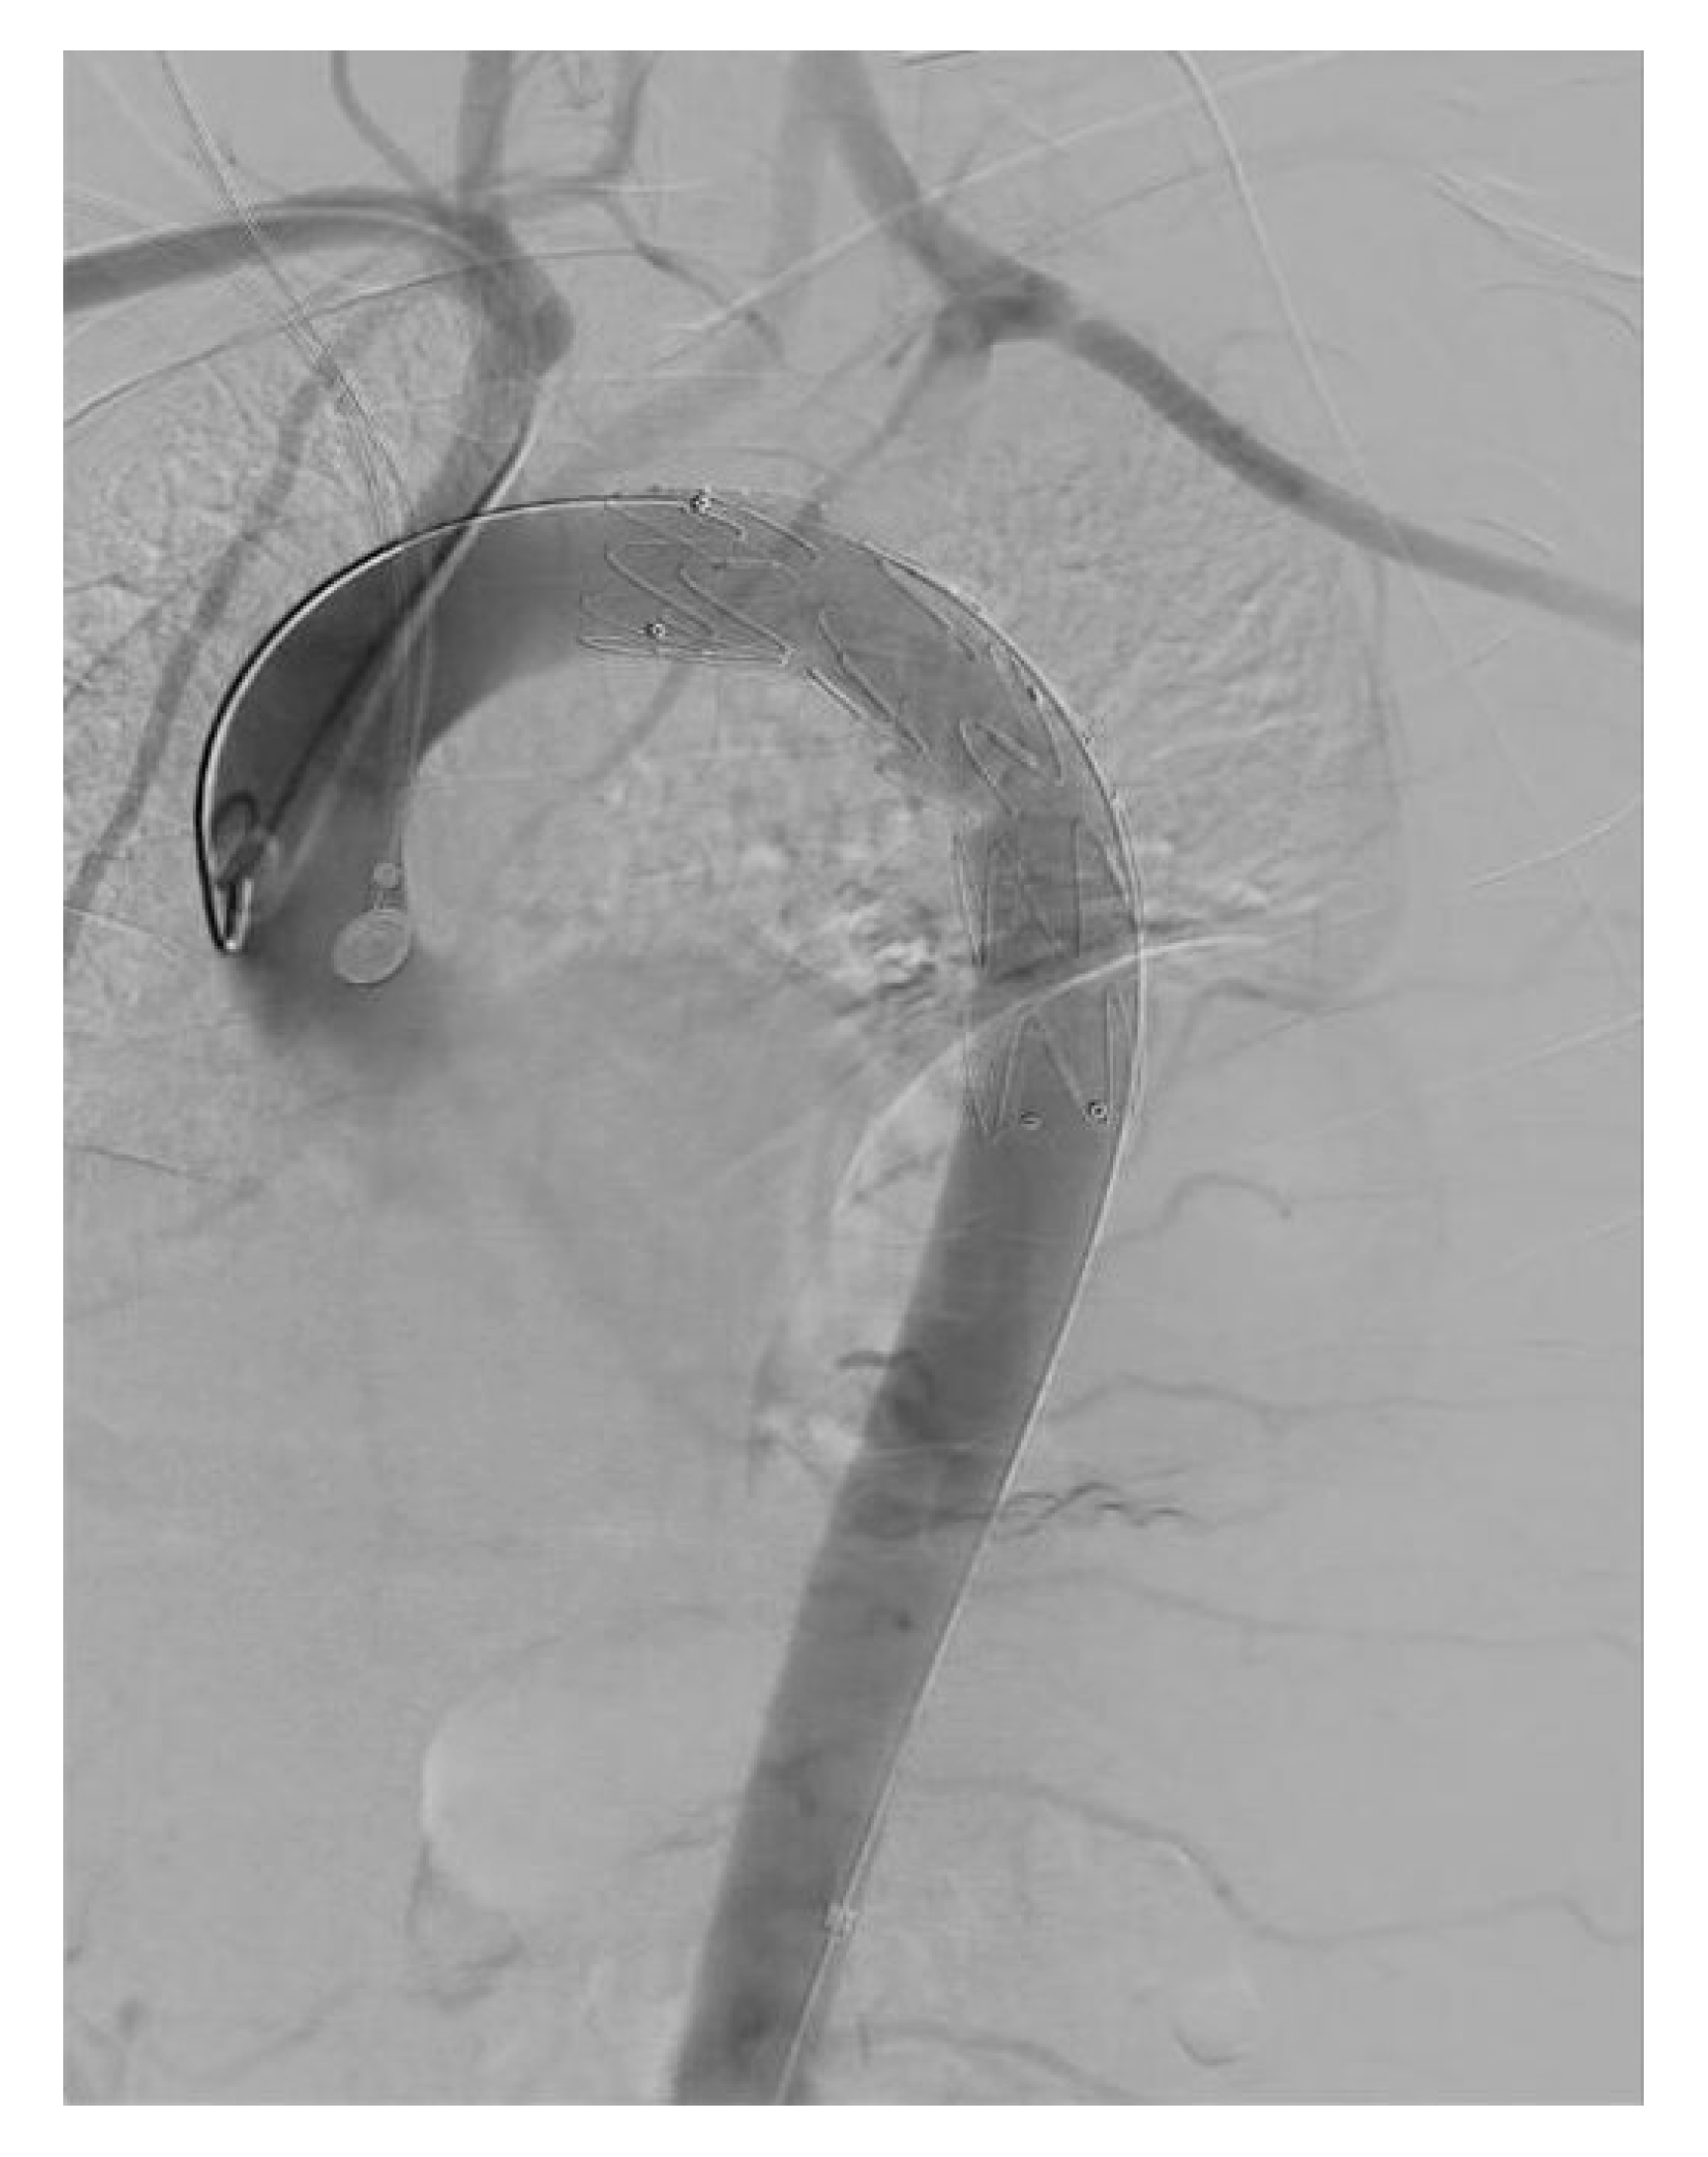

Reverse-Wire TEVAR for Subacute Type B Aortic Dissection with Severe True-Lumen Collapse: A Case Report

2. Case Report